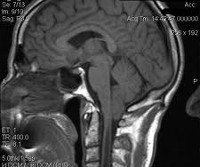

Аномалия Киари (мальформация Арнольда-Киари) - заболевание, при котором структуры головного мозга, расположенные в задней черепной ямке, опущены в каудальном направлении и выходят через большое затылочное отверстие. В зависимости от типа аномалия Киари может проявляться головной болью в затылке, болью в шейном отделе, головокружением, нистагмом, обмороками, дизартрией, мозжечковой атаксией, парезом гортани, снижением слуха и ушным шумом, нарушением зрения, дисфагией, дыхательными апноэ, стридором, расстройствами чувствительности, гипотрофией мышц и тетрапарезом. Аномалия Киари диагностируется путем проведения МРТ головного мозга, шейного и грудного отделов позвоночника. Аномалия Киари, сопровождающаяся стойким болевым синдромом или неврологическим дефицитом, подлежит хирургическому лечению (декомпрессия задней черепной ямки или шунтирующие операции).

Следует отметить, что МСКТ и КТ головного мозга при хорошей визуализации костных структур краниовертебрального перехода не позволяют достаточно точно судить о мягкотканных образованиях задней черепной ямки. Поэтому единственным достоверным методом диагностики аномалии Киари на сегодняшний день является магнитно-резонансная томография. Ее проведение требует обездвиженности пациента, поэтому у маленьких детей она проводится в состоянии медикаментозного сна. Кроме МРТ головного мозга для выявления менингоцеле и сирингомиелических кист необходимо также проведение МРТ позвоночника, особенно его шейного и грудного отделов. При этом проведение МРТ исследований должно быть направлено не только на диагностику аномалии Киари, но и на поиск других аномалий развития нервной системы, которые часто с ней сочетаются.